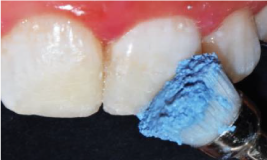

A 37% phosphoric acid gel was applied for 10 seconds over the enamel (figure 5a) then over the entire tooth for 20 other seconds. Then, the tooth was washed with an air–water spray. The entire tooth surface was air-dried and the exposed dentin surfaces were re-wetted with a disposable brush (Cavibrush, FGM Dental Products).

Figure 5a. Application of 37 % phosphoric acid gel over the enamel

Afterward, the adhesive system Adper Single Bond 2 (3M ESPE, St. Paul, MN, USA) was applied in two coats following the manufacturer’s guidelines (figure 5b).

Figure 5b. Application of the adhesive system Adper Single Bond 2